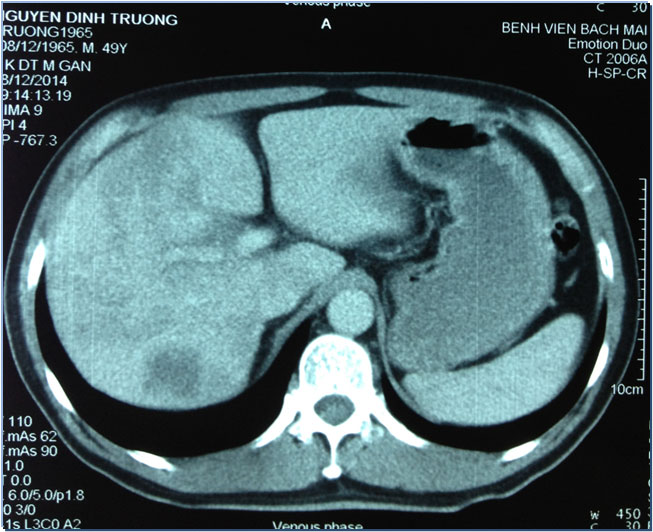

Hình ảnh khối u gan (sẫm màu bên trái) với kích thước 8,5 x 7,2cm trước khi điều trị của bệnh nhân.

Đây là một bệnh nhân nam (59 tuổi, Hà Nội) vào viện vì đau tức hạ sườn phải. 2 tháng trước khi vào viện, bệnh nhân có đau tức hạ sườn phải, người mệt mỏi, ăn kém, sụt 2kg/tháng. Sau khi phát hiện u gan tại một phòng khám tư, bệnh nhân đã vào BV Bạch Mai để khám. Tại đây bệnh nhân được phát hiện khối u rất to ở gan phải, với kích thước 8,5x7,2cm. Gan trái cũng được phát hiện khối u kích thước 3,1 x2,1cm.